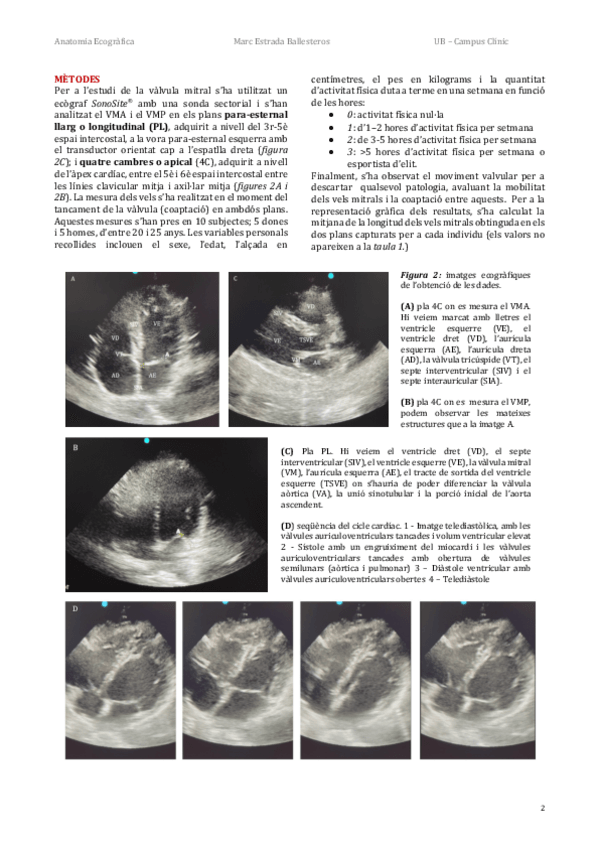

He publicado nuevos apuntes de 4º Enfermedades del Aparato Cardiocirculatorio: VELS-MITRALS-MARC-ESTRADA.pdf

4 páginas